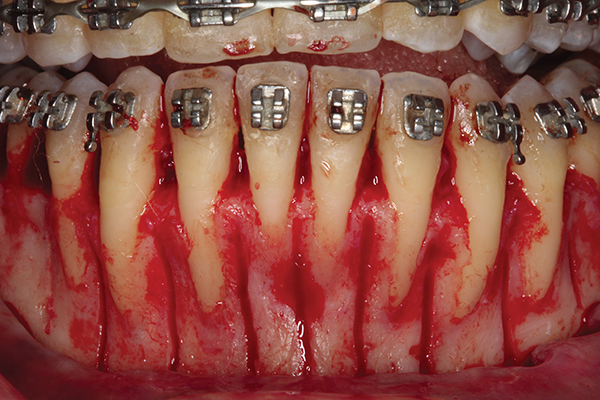

Fig 3. Corticotomy cuts performed.

Figure 3